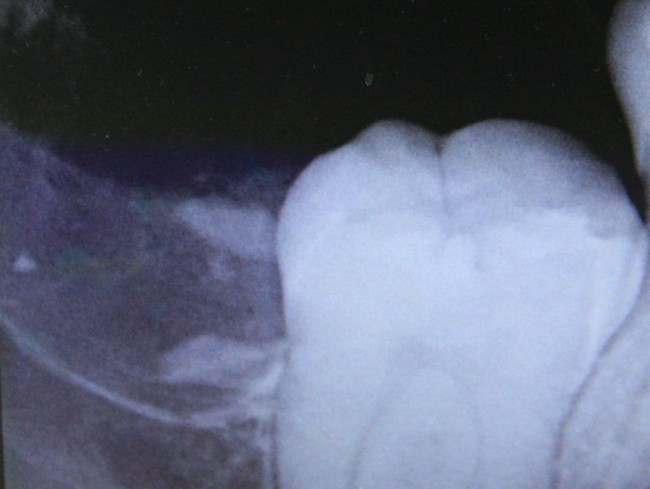

Однажды ко мне обратилась девочка по направлению от ортодонта. Принесла снимок:

Помимо аномального положения зуба мудрости есть еще одна проблема: восьмерка заблокировала седьмой зуб, в результате он не может прорезаться. В другой клинике ей предложили удалить два зуба, но она, по совету своего доктора, решила обратиться к нам в клинику.

Мы решили, что семерку можно вытянуть, если аккуратно удалить восьмерку.

Делаем контрольный снимок, чтобы убедиться в том, что мы не повредили семерку: